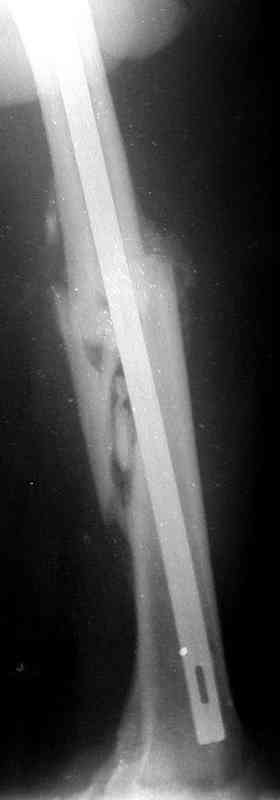

Больной А., 28 лет, поступил в НИИ им. Н.В. Склифосовского 22.12.99 после падения на улице. Жалобы на боли в области левого тазобедренного сустава и левом бедре. Из анамнеза следовало, что 20.06 во время прыжка с парашютом у него возник закрытый оскольчатый перелом средней трети левой бедренной кости со смещением отломков, по поводу чего в одной из ЦРБ Московской области через 3 дня после травмы был произведен открытый интрамедуллярный остеосинтез штифтом типа Кюнчера.

Послеоперационное течение было гладким. Больной ходил при помощи костылей с дозированной нагрузкой на оперированную конечность.При осмотре в НИИ им. Н.В. Склифосовского через 6 месяцев после травмы:

левое бедро и левый коленный сустав несколько увеличены в объеме, отечны, пальпаторно определяется болезненность в средней трети бедра;

по его наружной поверхности послеоперационный рубец - рана зажила первичным натяжением. При измерении длины бедер обнаружено укорочение левого бедра на 4,5 см. На рентгенограммах этого бедра: ось конечности правильная, отмечается захождение основных костных фрагментов по длине, проксимальный конец штифта выступает слишком медиально и высоко относительно большого вертела, периостальная мозоль незначительна.22.12 - через 6 месяцев после операции, произведенной в ЦРБ, нами по поводу замедленно консолидирующего перелома левой бедренной кости с ее абсолютным укорочением под наркозом произведена операция: удаление штифта, закрытый блокирующий интрамедуллярный остеосинтез перелома левого бедра штифтом без рассверливания (UFN) длиной 40 см, диаметром 10 мм с блокированием только проксимальных отверстий (динамический остеосинтез). Наложен аппарат Илизарова на 4 полукольцах с целью удлинения укороченного бедра. Послеоперационное течение без особенностей. Ежедневно осуществляли дистракцию отломков на 1 мм. Через 3 недели после операции больной выпи-сан на амбулаторное лечение с продолжением дистракции отломков. В течение 1,5

месяцев дистракции укорочение левого бедра удалось полностью устранить. 22.02.00, т.е. через 2 месяца после повторного остеосинтеза, больному произведено дистальное блокирование штифта двумя винтами и демонтирован аппарат Илизарова. В течение 2 недель после операции больной ходил с помощью костылей, потом 2 недели с тростью. Опороспособность и функция оперированной конечности полностью восстановились через 4 недели после операции.

Фиксаторы удалены через 12 месяцев после операции, выполненной по поводу замедленной консолидации перелома бедра с его укорочением.